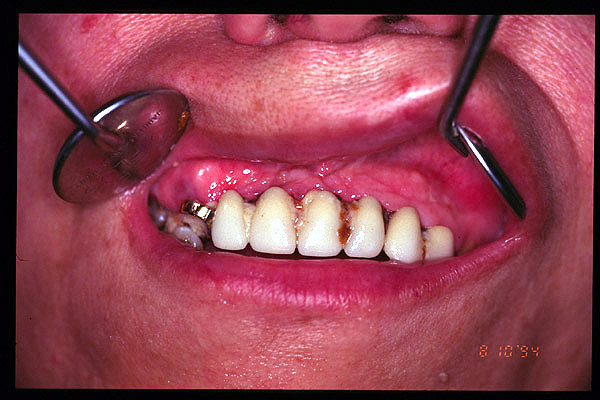

CM Hiperplasis por prótesis mal adaptada